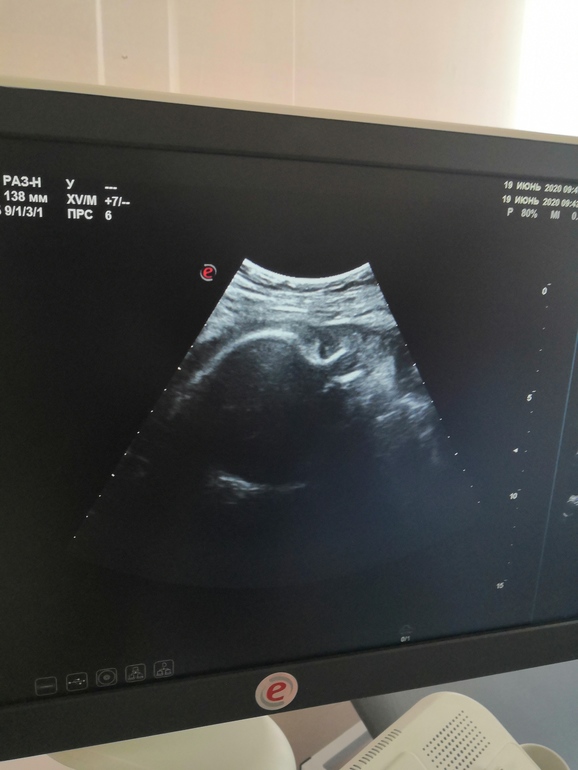

БеременностьВремя летит, я совсем не успеваю за ним следить. На прошлой неделе была на узи, малышка 1600, сказали, что будут ер, потому что плацента поднялась. Дали форточку малышки